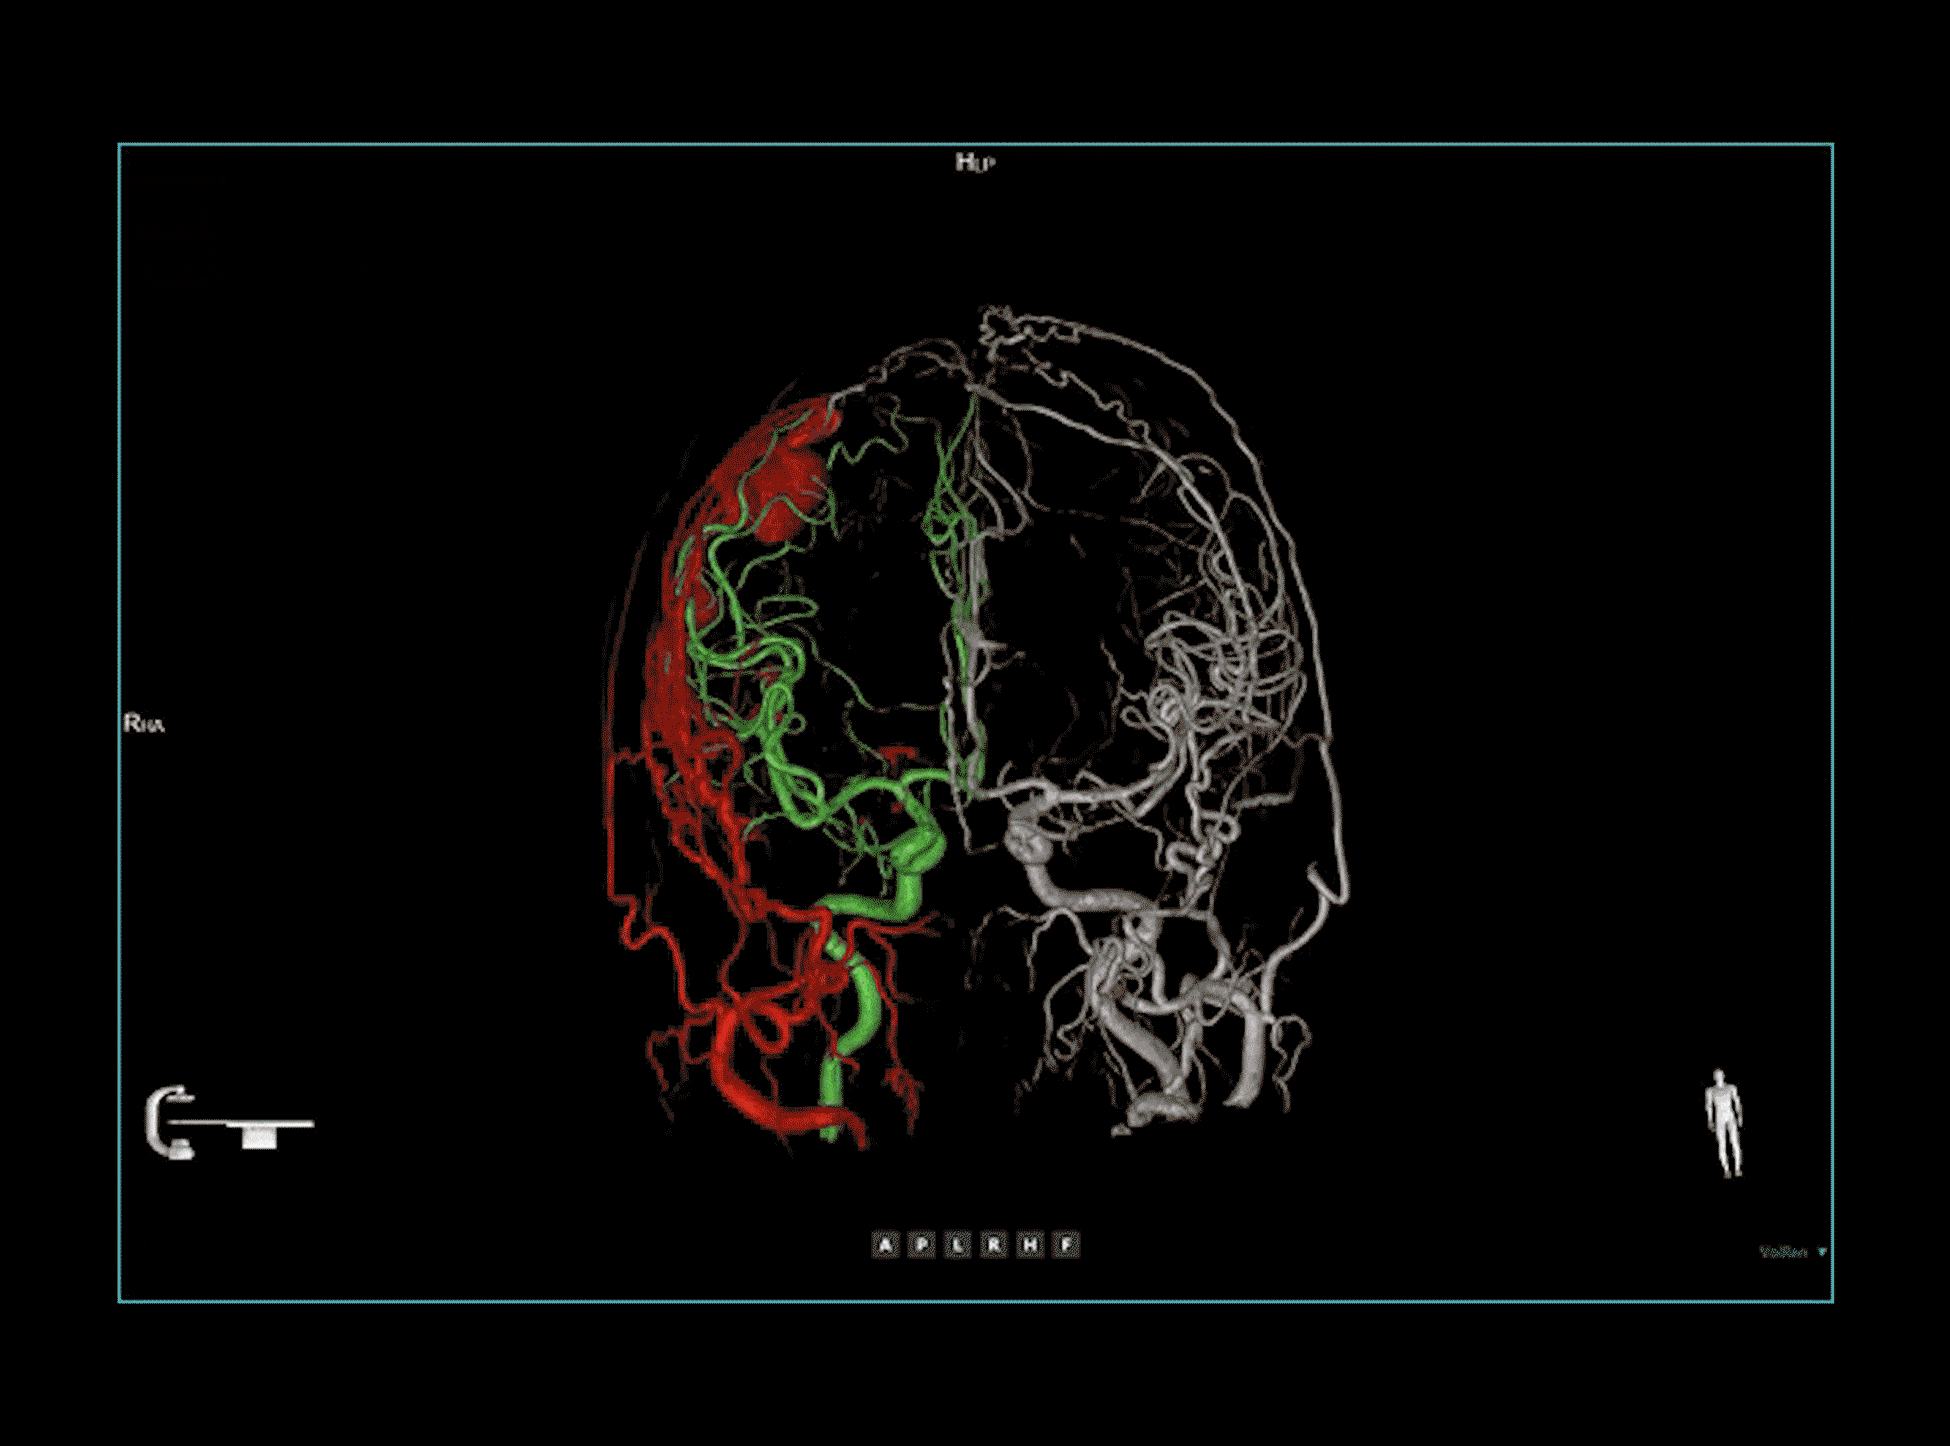

Intervenții neurovasculare

Fuziune multi-modalitate

Combină date din diferite volume sau modalități imagistice pentru a vizualiza cu claritate și precizie relațiile spațiale dintre structuri și vasele sanguine.

Fuziune multi-volum

După implantarea dispozitivului de deviere a fluxului pentru un anevrism intracranian, fuziunea multi-volum a evidențiat o aderență excelentă la peretele vascular, confirmând poziționarea optimă a dispozitivului.